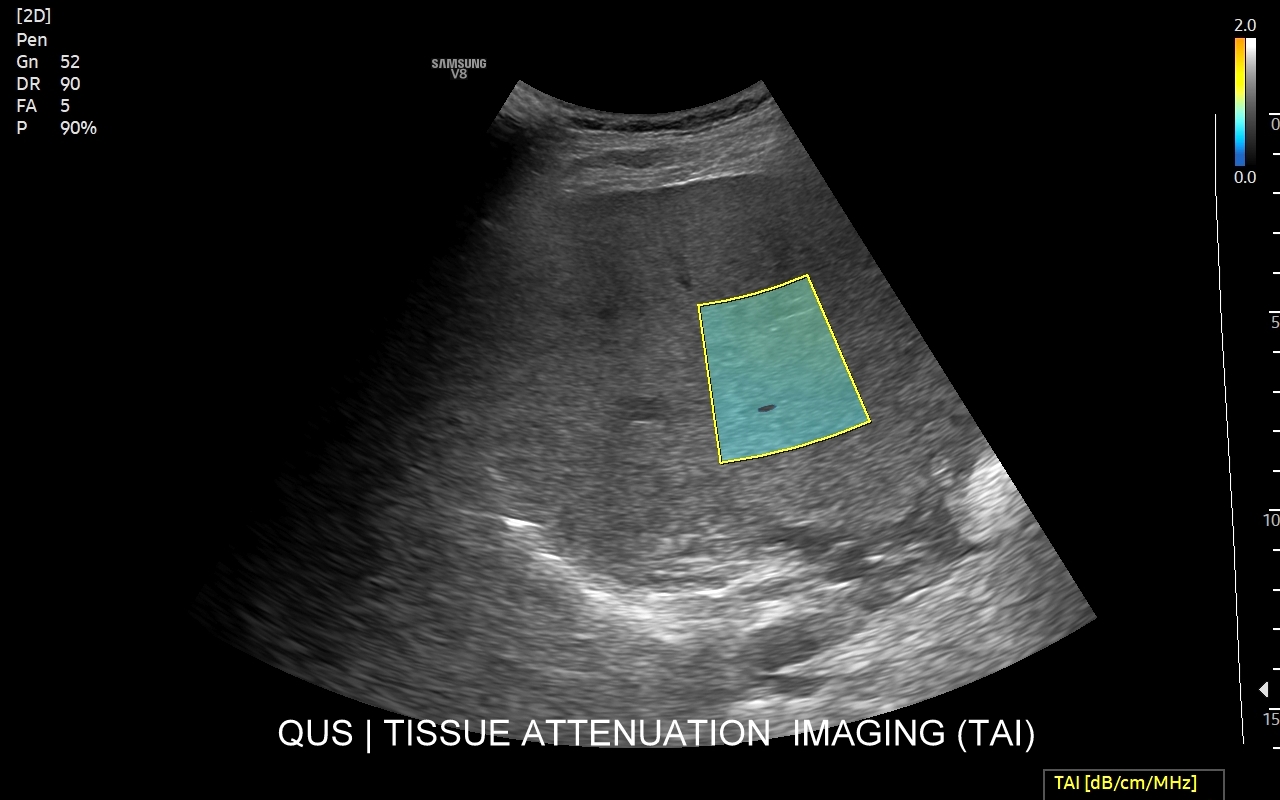

W ramach kompleksowej oceny wątroby elastografię 2D-SWE warto jednoczasowo połączyć z przeprowadzeniem badania USG przepływów wątrobowych oraz oceną stłuszczenia wątroby QUS w ramach kompleksowego badania MPUS brzucha. Podczas rejestracji zapytaj się o Multiparametryczne badanie USG / MPUS jamy brzusznej >